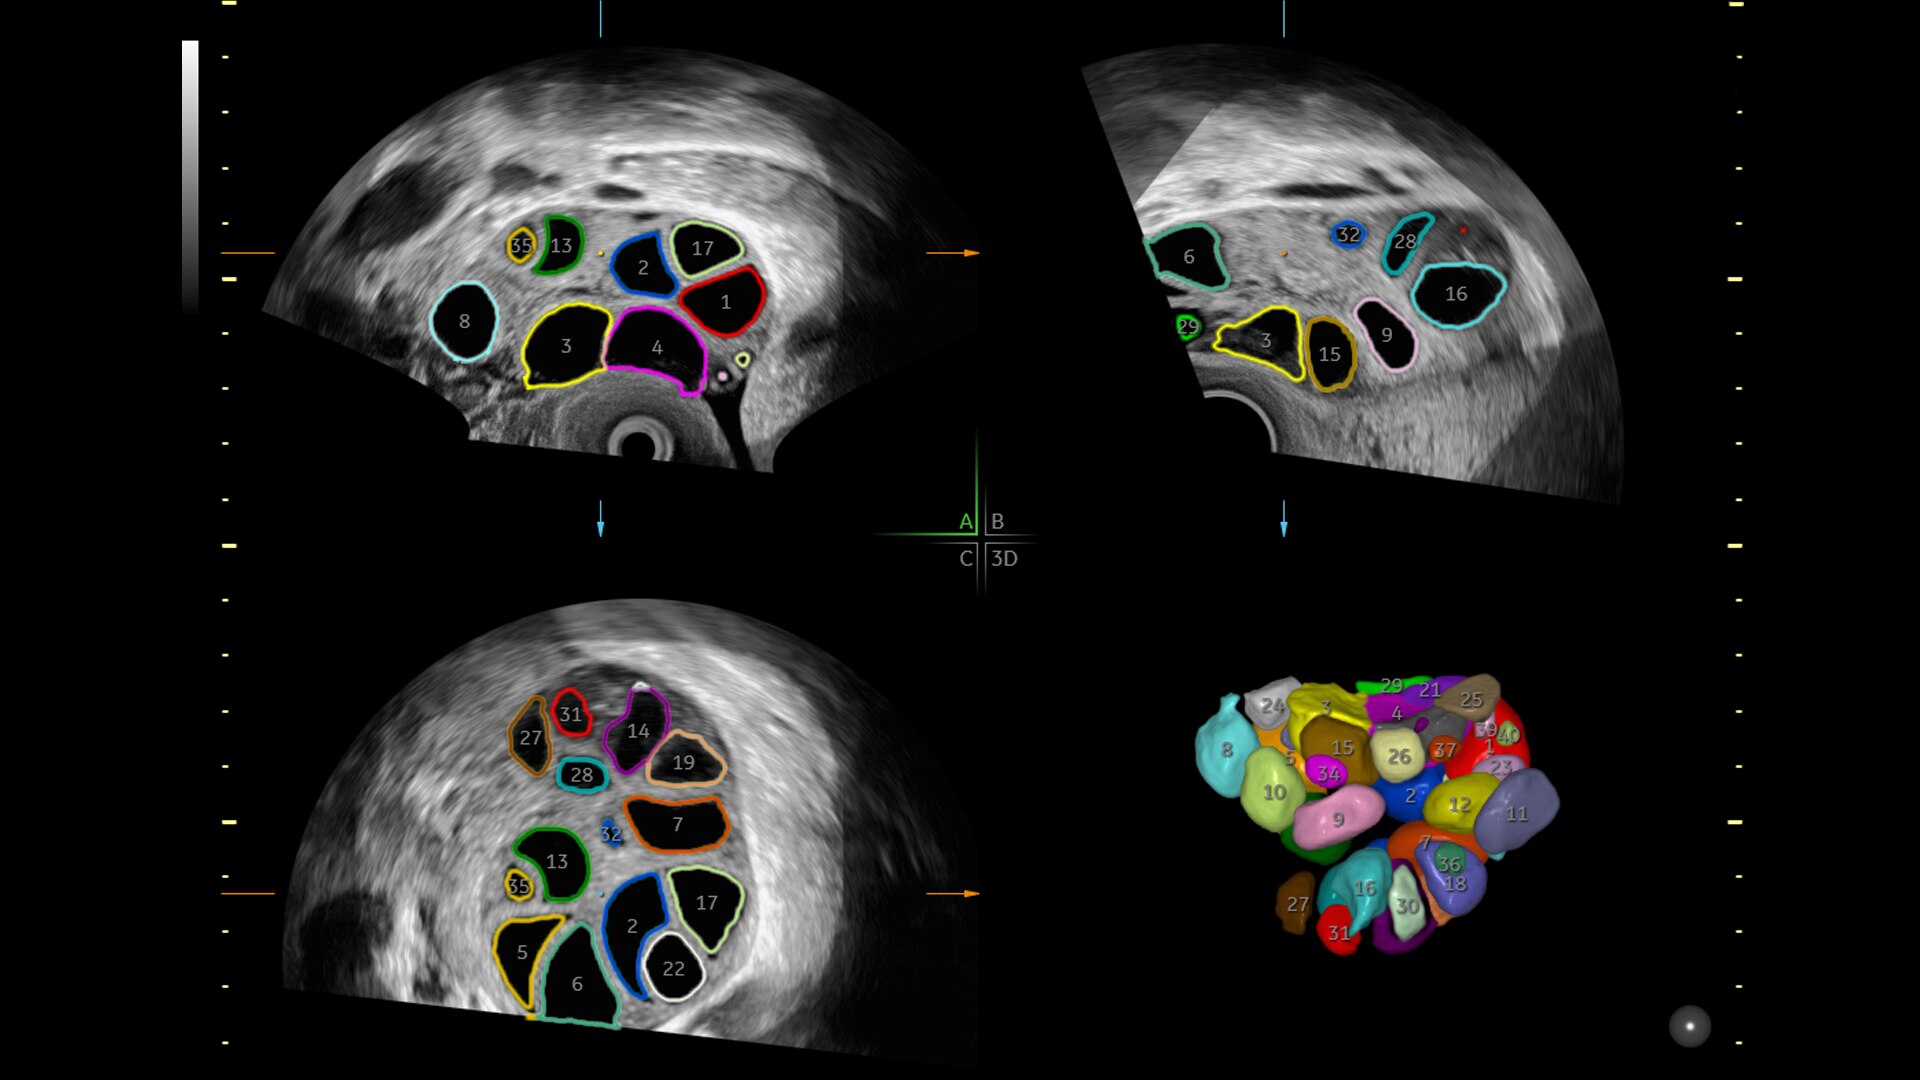

88% success rate identifying fibroids with Fibroid Mapping

SonoGYN

Combines our Uterine Trace tool and Fibroid Mapping feature, an AI reporting tool that standardizes and streamlines fibroid documentation by mapping, measuring, and classifying fibroids in 3D.